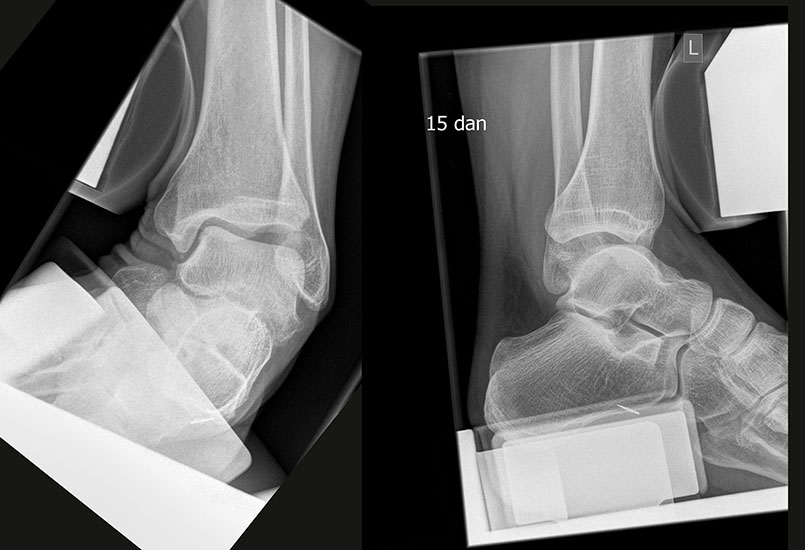

Röntgenaufnahmen dienen vor allem zum Ausschluss einer knöchernen Verletzung und umfassen Aufnahmen des Sprunggelenks anterior-posterior, lateral und 20° Innenrotation (Mortise view). Die über viele Jahre empfohlenen gehaltenen Aufnahmen haben ihre Bedeutung bei der Akutverletzung vollständig verloren, da sie die Behandlungsstrategie nicht beeinflussen (Abb. 2). Bei einer chronischen Instabilität liefen gehaltene Aufnahmen zusätzliche Informationen, wobei auch hier falsch negative Befunde möglich sind 26. Die höchste Zuverlässigkeit liefert die dynamische Untersuchung in Narkose 27

Die klinischen Beschwerden nach dem Distorsionstrauma liefern wichtige Anhaltspunkte für die Schwere der Verletzung. Kann nach einem Distorsionstrauma der Fuß voll belastet werden, ist eine knöcherne unwahrscheinlich 15. Bei einer Verletzung des lateralen Kapsel-Band-Apparats finden sich Schwellung, Hämatom (Abb. 2) sowie - je nach Ausmaß der Instabilität - ein positiver Talusvorschub und eine laterale Aufklappbarkeit 16.